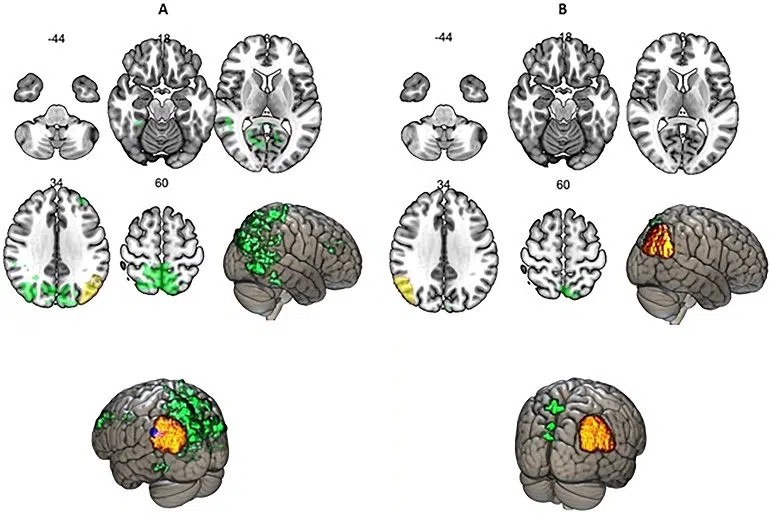

By looking at the connectivity patterns of the caudal inferior parietal cortex (IPC), however, the neurolinguists found a new functional brain category that has modulating functions; this brain area displays no similarities to task-related cortical areas, nor to brain areas that are active when the brain is not processingย external stimuli.

The cytoarchitectonically tripartite organization of the inferiorย parietal cortexย (IPC) into the rostral, the middle and the caudal clusters has been generally ignored when associating different functions to this part of the cortex, resulting in inconsistencies about how IPC is understood. In this study, we investigated the patterns ofย functional connectivityย of the caudal IPC in a task requiring cognitive control, using multiband EPI.

This part of the cortex demonstrated functional connectivity patterns dissimilar to a cognitive control area and at the same time the caudal IPC showed negative functional associations with both task-related brain areas and theย precuneusย cortex, which is active during resting state.

We found evidence suggesting that the traditional categorization of different brain areas into either task-related or resting state-related networks cannot accommodate the functions of the caudal IPC.

This underlies the hypothesis about a new brain functional category as a modulating cortical area proposing that its involvement in task performance, in a modulating manner, is marked by deactivation in the patterns of functional associations with parts of the brain that are recognized to be involved in doing a task, proportionate to task difficulty; however, its patterns of functional connectivity in some other respects do not correspond to the resting state-related parts of the cortex.